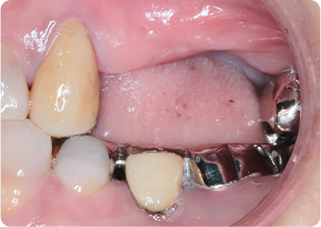

精密根管治療④

術前

術後

| 主訴 | 奥歯で噛むと痛い |

|---|---|

| 治療期間/回数 | 1ヵ月、3回 |

| 価格(税込) | 88,000円(税込) |

| リスク・副作用 | 病変再発、歯根破折の可能性 |

| ポイント | う蝕検知液を用い、むし歯の取り残しが無いようにし、ラバーダム防湿を行い、無菌的に根管治療を行った。根管充填材は、殺菌作用の強い保険適応外のMTAセメントを使用した。 |